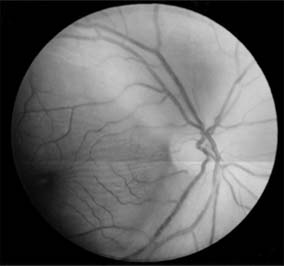

Figure 14-7

Figure 14-7: Arcuate neuroretinitis due to acute retinal necrosis syndrome. (Reproduced, with permission, from Margolis T et al: Acute retinal necrosis syndrome presenting with papillitis and arcuate neuroretinitis. Ophthalmology 1988;95:937.)